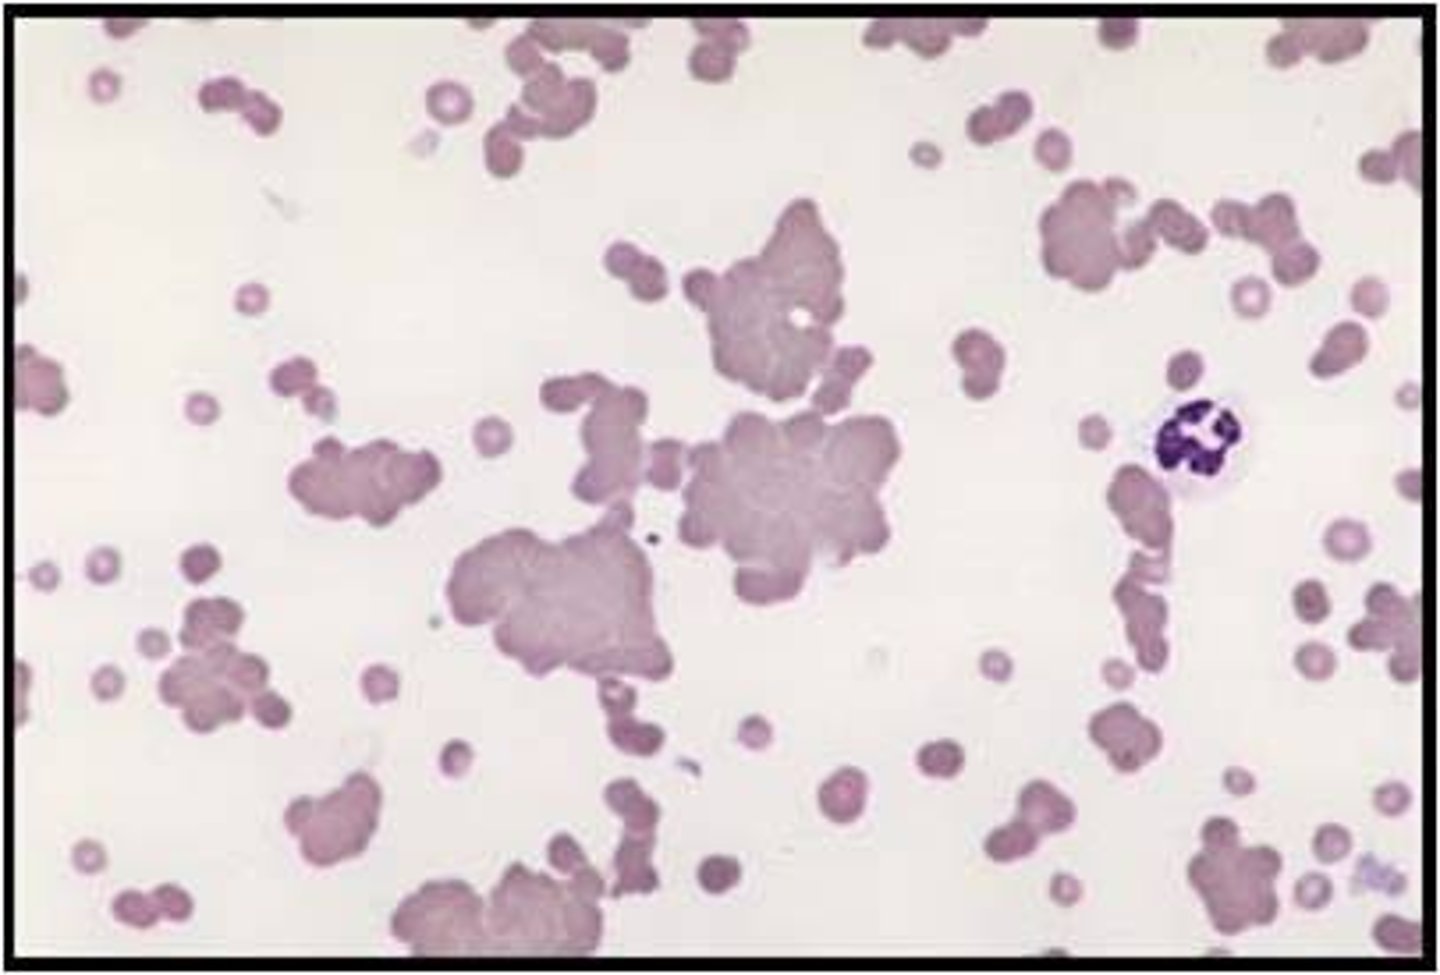

agglutination

unorganized 3D clumping of RBCs

rouleaux

organized, linear arrangement of RBC's

"coin stack"

3+ RBC's stacked